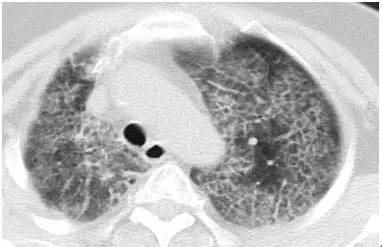

1. 肺泡蛋白沉积症

患者的肺像铺路石一样

2. 马赛克灌注(Mosaic perfusion)

这是肺内通气灌注不一致的表现,主要是小支气管炎症导致肺内局部积气,像马赛克拼图一样